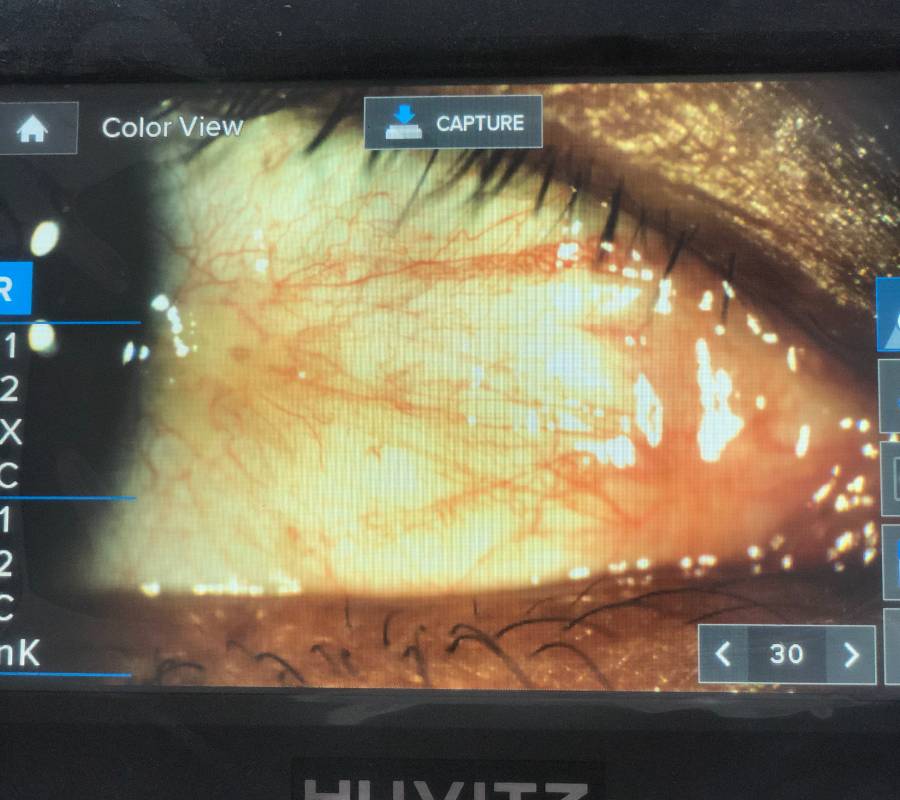

Pemeriksaan menyeluruh ke atas bahagian hadapan (anterior) dan belakang (posterior) mata—termasuk kornea, kanta, iris, retina serta saraf optik.